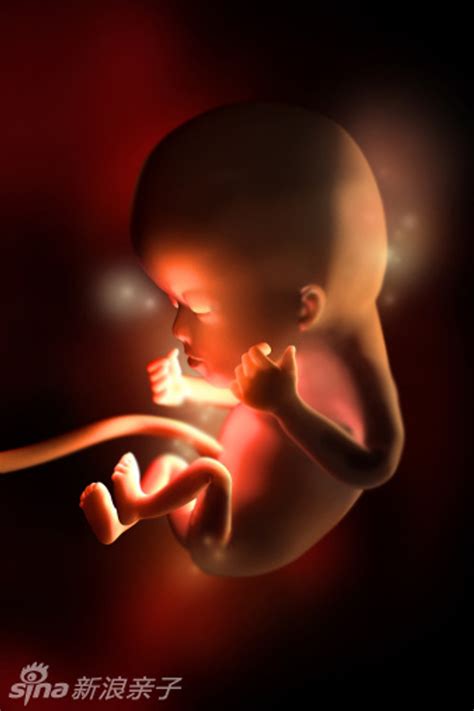

18周胎儿真实图图片(1)